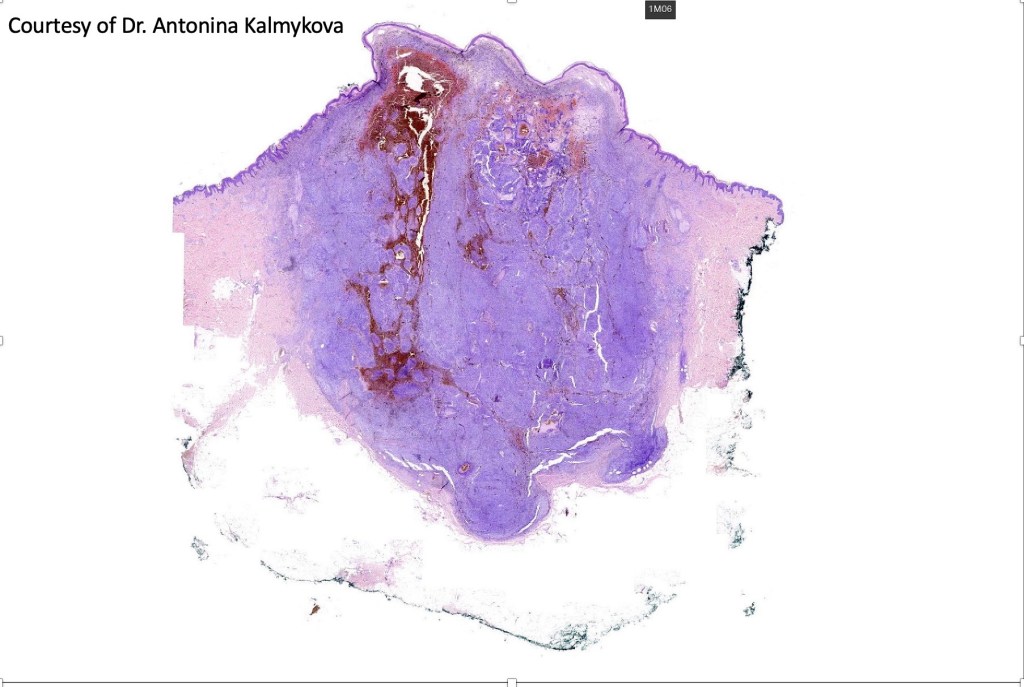

Cellular blue nevus

This uncommon most often devlops on the buttocks, sacrococcygeal region & distal extremities although it may be seen at just about any site. It shows a predilection for females and is diagnosed most often in the 2nd-4th decade. It presents as a blue-black/ or black nodule measuring 1-2 cm in dianeter. Similar to common blue nevus, the cellular variant can be encountered in a wide range of non-cutaneous locations.

•Most characteristic is the dumbbell silhouette although a plague morphology may also be encountered